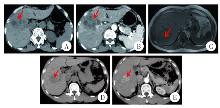

Fig. 1

Comparison of abdominal imaging features between fasciolosisis (A, B, C) and primary liver cancer (D, E) patients A: In the venous phase of abdominal CT, multiple quasi-circular hypodense lesions are visible in the right hepatic lobe, distributed in a clustered pattern; B: In the arterial phase of abdominal CT, hepatic lesions demonstrate no significant enhancement; C: In abdominal magnetic resonance imaging, hepatic segments 6 and 7 demonstrate patchy hypointense lesions; D: In the venous phase of abdominal CT, nodular hypodense lesions are observed in the right hepatic lobe; E: In the arterial phase of abdominal CT, significant enhancement is observed within the lesions in the right hepatic lobe.